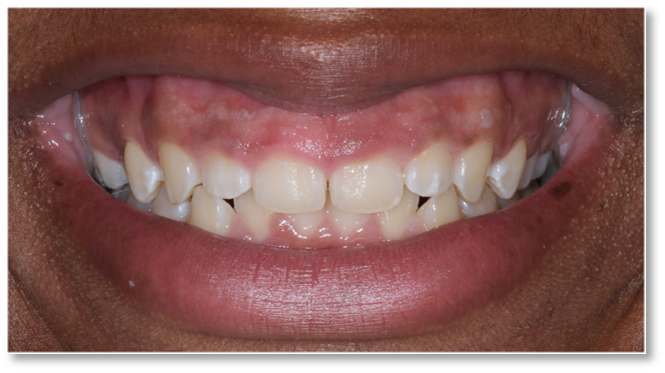

Before and after Periodontal Therapy

| Untreated severe gum disease | Gum disease treated and stabilised by Dr Halai |